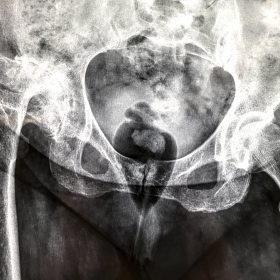

Διάγνωση- Σταδιοποίηση

Διακρίνονται σε 4 στάδια.

Στάδιο Ι. Στένωση του μεσαθριου διαστήματος

Στάδιο ΙΙ. Σκλήρυνση του υποκύμενου χόνδρου

Στάδιο ΙΙΙ. Σκλήρυνση του υπερκείμενου χόνδρου, καταστροφή του υποχόνδρινου οστούν, σχηματισμός οστεόφυτων, οίδημα αρθρώσεως και βραδυνός πόνος

Στάδιο IV. Οστική καθίζηση, καταστροφή μαλακών μορίων μυϊκών ομάδων, υπεξάρθρημα της αρθρώσεως και αλλαγή του μηχανικού άξονα